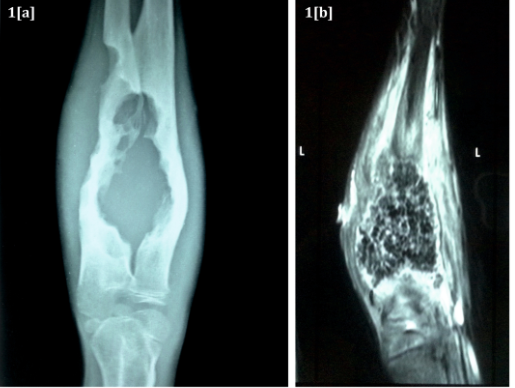

The patient was a young boy of 8years age who hailed from Siddharthnagar area of Uttar Pradesh state in India. He presented with pain, swelling and draining sinus in the right forearm for 4months. He had history of fever for 2months. He also gave a history of trauma to the forearm one year back with breach of skin and probably abscess formation which was treated with incision and drainage at his native place. The patient was symptomless for about 8months. Thereafter he developed swelling over the forearm and there were no external signs of inflammation. Local examination showed tenderness, swelling and a seropurulent discharge from a sinus at the drainage site. The supination-pronation movement of the forearm was greatly restricted. General examination did not reveal any abnormality. Hematological investigations revealed mild leukocytosis (WBC count 15000/mm3) and raised ESR (60mm at the end of 1hour). Other haematological parameters were within normal limits. Ray of the forearm revealed extensive bone destruction (Figure1A). The ultrasonography was suggestive of Infective osteomyelitis with a collection of 3.7x4.7cm. The MRI study showed soft tissue collections in proximal forearm between radius and ulna (Figure 1B).The patient then underwent surgical exploration which revealed cavity between radius and ulna which was full of a black mass. The mass was composed of abundant black grains which may have been discharged in the bony cavity from the surrounding soft tissues. The cavity was further being expanded by the growing mass of fungal grains. Black grains were also observed interspersed in the surrounding tissue. (Figures 2A) (Figure 2B). The debrided material was received for fungal culture. When observed in 10% potassium hydroxide, it showed plentiful brown cementing material interspersed with fungal hyphae (Figure 2C). On culture, a slow growing mould was observed on Sabouraud’s dextrose agar at both 260C and 370C, which was tan at first becoming brownish later. A diffusible brown pigment was observed in the agar and the fungus was identified as Madurella mycetomatis (Figures 3A) (Figure 3B).1

Figure 1A X ray of forearm showing extensive bone destruction with cortical irregularity and sclerosis.

Figure 1B MRI showing massive soft tissue collection between radius and ulna.